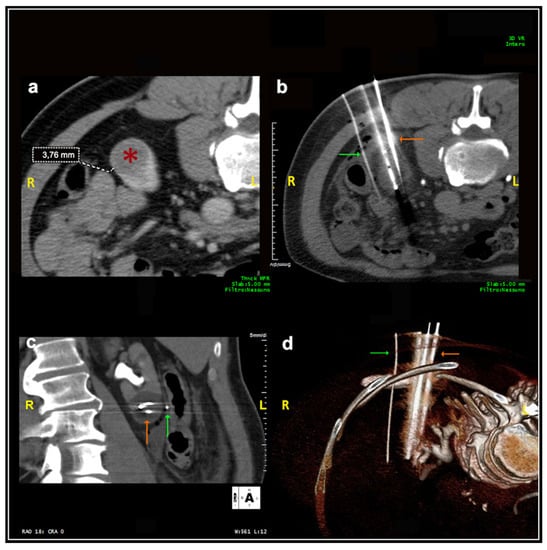

Most patients (87.4%) were treated prone. Twenty patients were treated in the oblique or lateral decubitus position (Figure 1). Only two treatments were carried out with the patient supine. Local anesthesia was mostly sufficient for the large majority of the procedures and mild conscious sedation was administered if needed. One patient required general anesthesia for the impossibility to collaborate with breath holds during the procedure because of dementia. In most cases, one lesion was treated in each procedure. In five patients, two lesions were treated in the same procedure, and, in another two patients, three lesions and four lesions were treated in a unique procedure, respectively. A median of two cryoprobes were used for each intervention (range: 1–8). Eight cryoprobes were required for the treatment of one of the largest tumors (5.4 cm), which revealed to be a clear-cell carcinoma at biopsy. The procedure was technically successful, and no complications occurred. Eighty-nine lesions required a complex cryoprobe approach. Hydro-dissection was necessary for the treatment of 13 tumors due to the vicinity of the bowel that could not be displaced after changing the position of the patient (Figure 2). In two cases, emptying of a cyst adjacent to the lesion was deemed necessary. Only one patient required a trans-hepatic approach (Figure 3). The procedures had a median duration time of 84 min (range: 40–153). Data on radiation exposure was available for 113 out of 138 patients with a median radiation exposure of 43.7 mSv.

Figure 3. Male, 78 years old. (a) The initial scan shows a lesion (*) located at the upper pole of the right kidney covered by the costophrenic sinus posteriorly (white arrow) and the hepatic parenchyma laterally. (b,c) The lesion was adequately treated with two cryoprobes inserted through the hepatic parenchyma in order to avoid pneumothorax. No complications occurred.